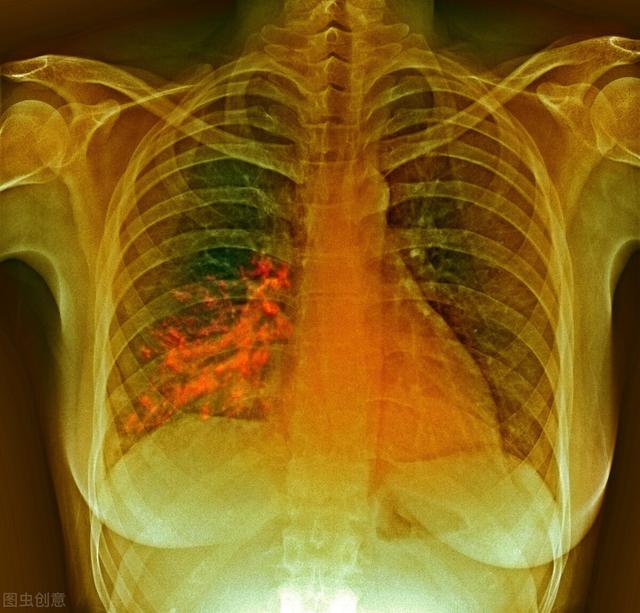

呛咳会导致食物进入气道,沿气道进入肺脏,这些食物残渣对于无菌环境的肺而言,属于感染源,会导致肺部感染,引起吸入性肺炎,出现发热、咳嗽、咳痰、喘憋、气短,严重的危及生命。鼻饲饮食,可避免呛咳发生,减少肺炎几率。